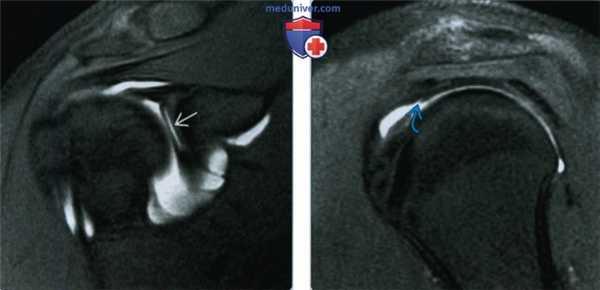

(Слева) На рисунке показан разрыв передне-верхней губы с неровными краями и кровотечением. Такие разрывы часто определяются при микронестабильности и поэтому их необходимо отличать на МРТ от более частых вариантов нормы передневерхней губы.

(Справа) На осевой МР-артрограмме Т1ВИ FS y пациента 21 год ас микронестабильностью после острой травмы определяется разрыв передне-верхней губы, а также травма капсулы с утечкой контраста в около-капсульные мягкие ткани.

(Слева) На фронтальной косой МР-артрограмме Т1ВИ FS y бейсбольною питчера 17 лет с симптомами микронестабильности видно подрезание губы, что указывает как на подгубное отверстие, так и разрыв передне-верхней губы.

(Справа) На сагиттальной МР-артрограмме Т1ВИ FS у этого же пациента определяется частичный малый разрыв суставной поверхности по толщине выступающею края сухожилия надостистой мышцы. На операции был выявлен разрыв губы; это сочетание обусловливает повреждение верхней губы и передней манжеты.